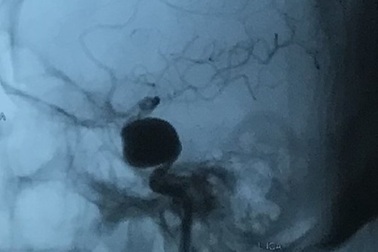

Hoảng với khối phình mạch máu não khổng lồĐi khám vì mờ mắt, nữ bệnh nhân được bác sĩ chẩn đoán có khối phình động mạch khổng lồ, kích thước 6cm, trong khi bình thường chỉ 2-10mm.